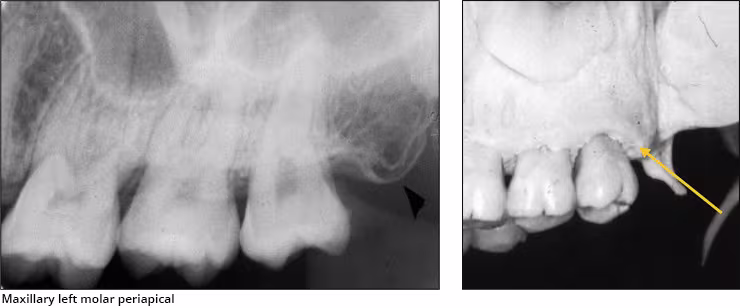

Coronoid process – The coronoid process of the mandible is the triangular bony portion of the anterosuperior aspect of the ramus (Figure 17 A). This mandibular structure can be recorded on maxillary molar periapical images as the ramus moves forward when the patient’s mouth is open. It appears as a bilateral triangular or thumb-like radiopacity on posterior maxillary images (Figures 17 B&C). The triangular portion projects forward toward the midline. The coronoid process is the only mandibular structure recorded on maxillary molar periapical images.

Figures 17 A,B,C: Coronoid Process